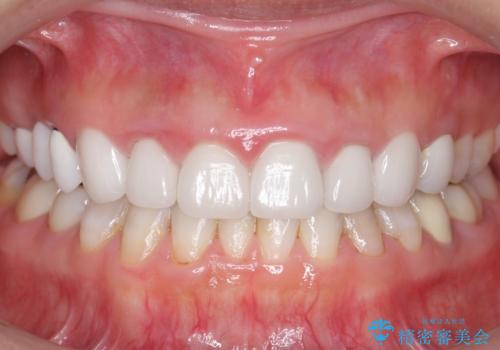

自然な仕上がりと咬み心地に喜んで頂けました。

クラウンの種類:オールセラミッククラウン スタンダード